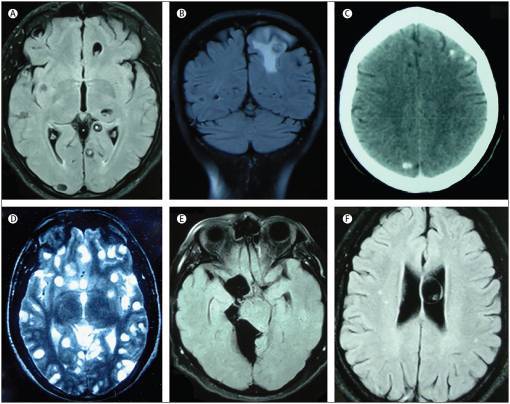

촌충을 직접 분리해 내기는 어렵기 때문에 영상학적 및 혈청학적 검사를 통해 진단합니다. 영상학적 검사상 뇌 CT 혹은 MRI 상 결절이 다량으로 관찰되며 hole-with-dot라는 특징적인 소견이 나타날 수 있고, LLGP를 이용한 혈청학적 검사상 촌충에 대한 항체를 검출할 수 있다는 것이 특징입니다. 나아가 드라마 속에서처럼 허벅지에서 유충의 흔적을 발견할 수 있고, 이는 때때로 진단에 유용한 정보로 사용될 수 있습니다.

뇌유낭미충증의 영상 소견

알벤다졸(albendazole) 혹은 프라지콴텔 (praziquantel)등의 구충제를 이용해 치료하는 것이 일반적입니다. 경우에 따라 염증을 조절하기 위해 스테로이드를 병행하거나, 뇌압을 낮추기 위해 배액관을 삽입하거나 낭종을 직접 제거하는 수술이 시행될 수도 있습니다.